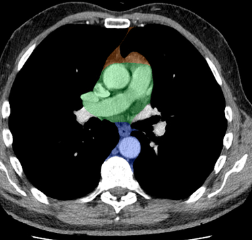

Anterior mediastinal mass

A

1. Thyroid (goitre)

2. Lymphoma (Hodgkins usually)

3. Teratoma/Seminoma

4. Thymoma